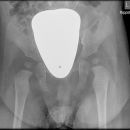

Beckenübersicht a.-p.

Fraktur, Luxation und degenerative Veränderungen (Coxarthrose)

Das Becken stellt sich vollständig, symmetrisch und gleichmäßig gut belichtet dar, einschließlich beider Hüftgelenke und der Trochanteren. Trochanter major darf den Schenkelhals nicht überlagern und der Trochanter minor ist gerade erkennbar.